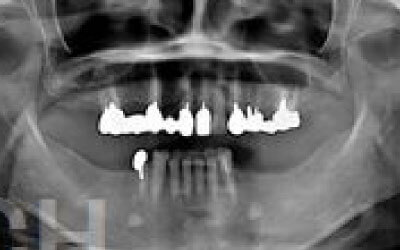

今回のご質問ですが、抜けた部分の骨が薄いなどの理由で「インプラントはできない」と言われた可能性があります。

前歯はもともと骨が薄く、歯が抜けると時間の経過とともにさらに骨が痩せてきてしまうので、インプラント治療の難易度が高い場所です。

ただ結論からお話すると、インプラント治療は可能です。

なぜなら、もし仮に骨が薄くても、骨の治療によって厚みが増せば、安全にインプラント治療が行えるからです。

1)インプラント治療を行う前に、骨の治療が必要かもしれません。

2)骨の治療から始めると、その分、治療期間が長くなります。

4)骨の状況をしっかり把握するためにも、CT撮影が必須となります。